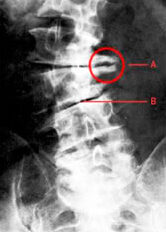

A espondilólise é uma alteração da coluna vertebral em que não há fechamento do arco posterior.

A espondilolistese é um deslizamento de um corpo vertebral no sentido anterior, posterior ou lateral em relação à vértebra adjacente, ocasiona dor , que piora com a movimentação e esforços físicos.

Os Osteófitos são formações ósseas que ocorrem na coluna vertebral com aspecto de gancho e muitas vezes se assemelham a um bico, daí popularmente serem conhecidos como Bico de Papagaio. Geralmente em casos de problemas reumáticos, como, por exemplo, a osteoartrose lombar e cervical. Este Crescimento ósseo ocorre como uma resposta do organismo a uma agressão, (vícios posturais, trauma, sobrepeso e alterações degenerativas).